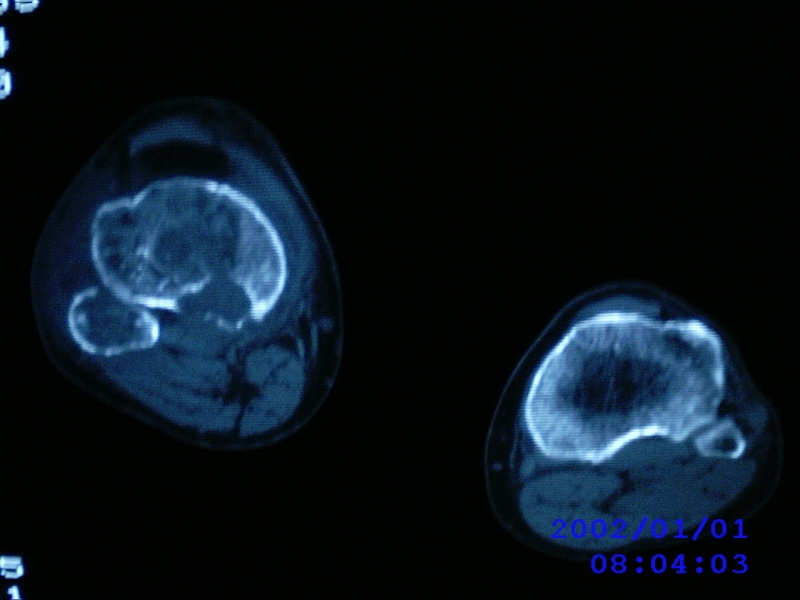

患者,男性,57岁,右侧膝关节疼痛伴肿脹10余年,加重一个月。

关节积液,关节间隙变窄,边缘骨破坏。考虑膝关节tb

关节积液,关节间隙变窄,骨质疏松,多发骨破坏,边缘轻度硬化,近端胫腓骨髓腔软组织充填,患者病史较长,支持考虑结核

有皮质的破坏~有死骨存在

结合临床表现,考虑结核。。。。课医照个胸片

多发骨破坏,骨质疏松,关节积液。考虑右膝关节结核。